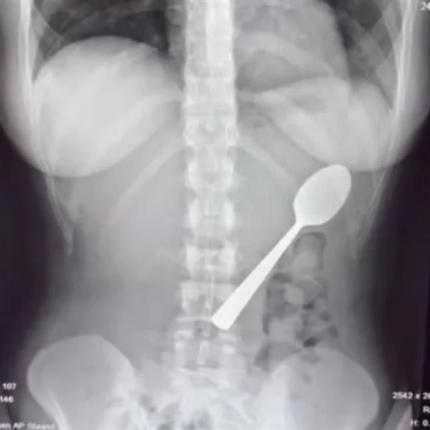

Ο ασθενής εισήχθη αρχικά στο νοσοκομείο με έντονο πόνο στο στομάχι, με τους γιατρούς να πιστεύουν πως πρόκειται για όγκο, όμως οι ακτινογραφίες έδειξαν ένα… σύμπλεγμα ξένων αντικειμένων.